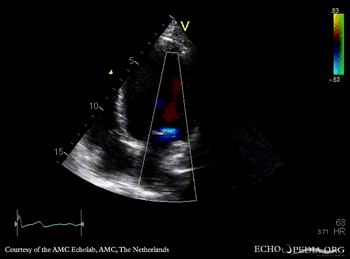

PLAX: Color Doppler, moderate mitral regurgitation A4CH: dilated poor left ventricle